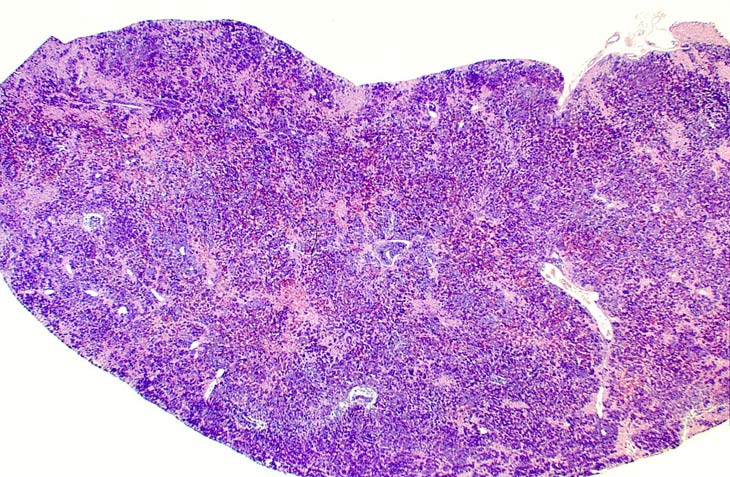

Erythroleukemia is a spontaneous hematopoietic neoplasm of Tg.AC mice characterized by marked hepatomegaly. The affected liver is infiltrated by metarubricytes and less differentiated erythroid precursors.

Examples of erythroleukemia in a Tg.AC mouse.